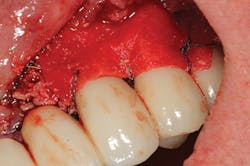

Late implant complications occur after the implant has integrated and the final prosthesis has been placed. Recognition of these complications via radiographic and clinical analysis is extremely important since many of these problems can be corrected if detected early. On the other hand, if allowed to progress, a minor complication can often result in loss of the implant and/or prosthesis. Late complications of the dental implant fall into the category of biologic or mechanical complications. Late biologic complications are those in which the peri-implant soft and hard tissues are affected. Peri-implant mucositis describes a reversible inflammatory reaction in the mucosa adjacent to an implant,(8) a term that has become known as implant gingivitis. Studies show that the prevalence of peri-implant mucositis can be as high as 50% to 80% of implants in function(9) with the etiology of peri-implant mucositis being bacterial plaque. Typical clinical presentation includes erythema, edema, swelling, and redness (Figs. 1 and 1a). Although bleeding upon probing and increased probing depths are not always indicative of peri-implant mucositis,(10) the absence of these two factors usually means implant health.(11)

Peri-implantitis has been defined as an inflammatory process that affects the tissues around an osseointegrated implant in function and, like periodontitis, results in loss of supporting bone6 (Figs. 3 and 3a). The prevalence of peri-implantitis has been shown in some studies to range from 11% to as high as 47% of implant sites analyzed.(16) Most literature reviews agree that once bone loss has occurred around an implant, nonsurgical therapy is not as effective as surgical treatment.(17) Surgical intervention by the dentist or specialist includes raising a full thickness flap around the affected dental implant in order to completely expose the dental implant surface (Fig. 4). Mechanical debridement with hand and high-speed instrumentation as well as irrigation with various medicaments is advocated in order to detoxify the implant surface and alleviate bacterial contamination. After decontamination, the flap can be apically or coronally positioned. In addition, various regenerative technologies, including bone and soft-tissue grafts, growth factors, and barrier membranes have been used to rebuild lost tissue support around the dental implant (Figs. 5 and 5a). Different methods of guided bone regeneration around implants affected with peri-implantitis were demonstrated, and the results have been shown to be stable for a follow-up period of up to seven years.(18) That being said, no gold standard of peri-implant disease has been documented and "available evidence does not allow specific recommendations for the therapy of peri-implantitis."(19)